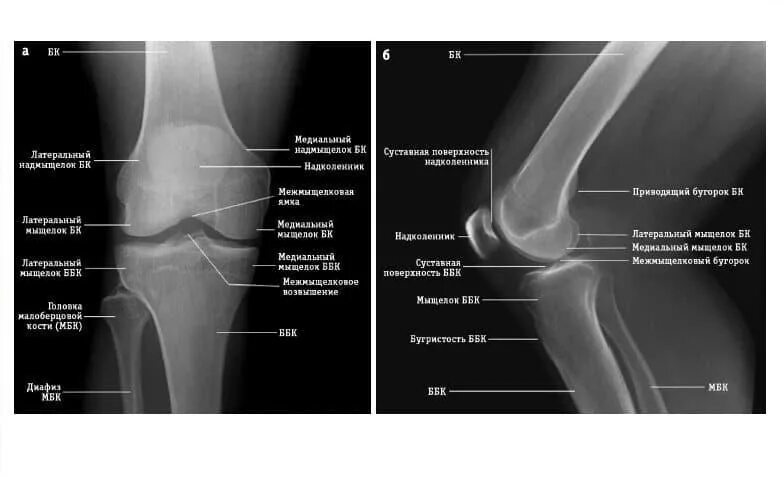

Вывих надколенника код мкб 10